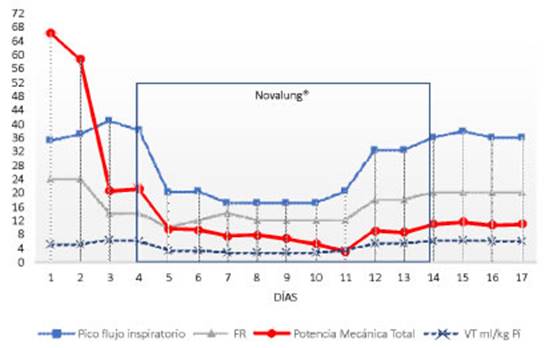

(Figura 1).

El

con EA. Se observó una notable correlación entre el PEEPi y la Pmáx de la

vía aérea, las que disminuyeron drásticamenÂte cuando

logramos bajar la FR, reducir el VT

y prolongar el tiempo espiratorio (relación I:E = 1:7) después de instalar el Novalung®.

Luego de introducir este dispositivo se pudo reducir la FR de 24

rpm a 10 rpm, con lo cual la PEEPi se redujo de 15

cmH2O a 6 cmH2O.

Al analizar la PM en sus componentes específiÂcos: potencia

elástica estática (asociada a la PEEP), potencia elástica

dinámica (asociada al VT)

y “poÂtencia resistiva” (vía aérea nativa), observamos que la

caída de la PM se debió principalmente a la reducción del

componente resistivo, que en el estaÂtus asmático sería

teóricamente el más importante. En nuestro caso, este componente

alcanzó más del 80% de la PM total en el primer día

(Figura 2).

se observó el impacto de la reducción de FR y del VT en la “potencia resistiva”, la

cual disminuyó de 58 J/min a 14,6 J/min.

Por otra parte, el flujo pico también es una variable

importante en el desarrollo del daño epitelial alveolar (Figura 3), en

consecuencia, la reducción del flujo inspiratorio evita la

disrupción del epitelio respiratorio. Este fenómeno ha sido

demostrado en un modelo in vitro por TschumÂperlin.11 En nuestro paciente, la

disminución de la FR permitió prolongar el tiempo espiratorio,

con lo que se pudo prolongar simultáneamente el tiempo inspiratorio y

reducir así el flujo pico.

El componente resistivo de la PM debe ser analizado siempre en

pacientes con obstrucción de la vía aérea. Al analizar los

componentes por separado, el componente resistivo (línea roja) se

destaca claramente como el principal generador de PM en este tipo de pacientes

(Figura 2).